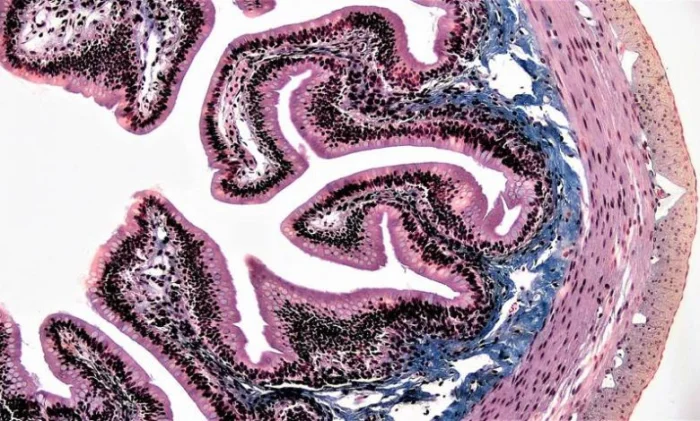

Простой столбчатый эпителий кишечника. 10-кратное увеличение.[/caption]